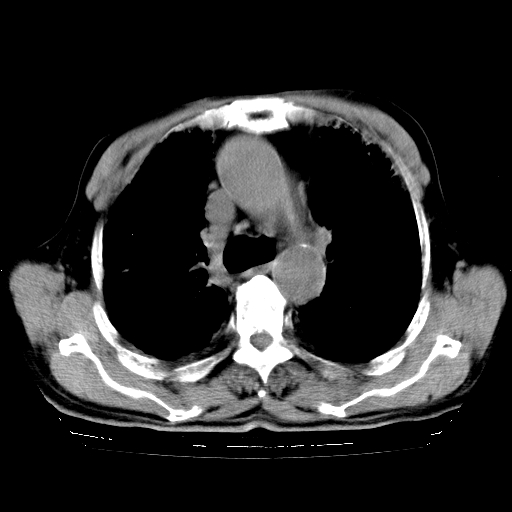

标题: CT25149:男,69岁,反复咳嗽、咳痰五年余,呼吸困难三天。 [打印本页]

男,69岁,反复咳嗽、咳痰五年余,呼吸困难三天。

慢支伴感染、肺气肿、肺心病

慢支伴感染、肺气肿、肺心病!支持!另:间质纤维化!

两肺间质性炎症并感染,左上叶肉芽肿

考虑慢性间质性肺炎并肺间质纤维化。

慢支伴感染、肺气肿、肺心病。双肺间质性改变(间质纤维化)。